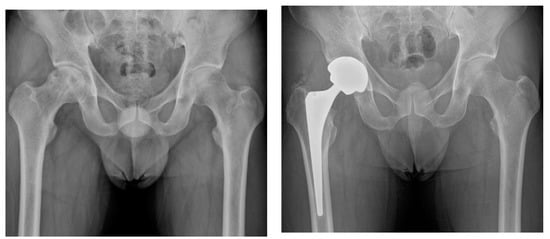

There were no cases of 90-day mortality in either group, while one unplanned readmission was identified in the brain tumor group; the patient was a 33-year-old woman with moderate cognitive impairment and visual loss in the right eye after resection of craniopharyngioma in the suprasellar region. She developed a non-traumatic hip dislocation on the 15th postoperative day after THA, which was treated successfully by closed reduction and abduction brace application (Figure 2). A PFF (Vancouver B2) in the control group was managed by isolated stem revision using a long modular stem, while no reoperations were performed in the brain tumor group. Symptomatic deep vein thrombosis (DVT) and pulmonary embolism (PE) were not observed in both groups. Overall major complication rates were 2.9% in the brain tumor group and 1.5% in the control group (P-value = 1.000).

The rates of the appearance of radiolucent lines in radiographs around the acetabular cup were 5.9% and 4.4% in the brain tumor and control groups, respectively (P-value = 1.000); they were 8.8% and 5.9% around the femoral stem (P-value = 0.683) (Table 6). There was no complete radiolucency in either group, suggesting acetabular loosening. All femoral radiolucent lines were confined to one or two zones. More HO was observed in patients with brain tumors compared to in the controls (32.4% and 10.3%, respectively; P-value = 0.006), all of which were classified as Brooker grade 1 or 2 (Figure 3).

Figure 3.

(A) Preoperative hip radiograph of a 41-year-old man who had undergone surgical removal of meningioma in the right frontal lobe 4 years prior to THA, demonstrating collapsed osteonecrosis of the right femoral head. (B) Five-year postoperative radiograph demonstrating stable implants with Brooker grade 2 heterotopic ossification. The patient had no pain and was satisfied with the outcome.